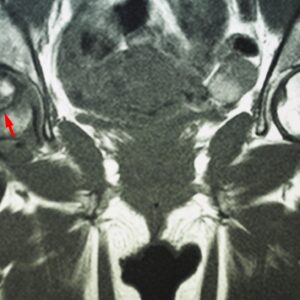

Hip Patient informationOverview Meta Description: Explore an in-depth scientific overview of Developmental Dysplasia of the Hip (DDH), its causes, risk factors, diagnosis, treatment, and long-term outcomes. SEO Keywords: developmental dysplasia of the hip, DDH, congenital hip dislocation, infant hip dysplasia, Pavlik harness, hip surgery, orthopaedics, musculoskeletal disorders Introduction Developmental Dysplasia of the